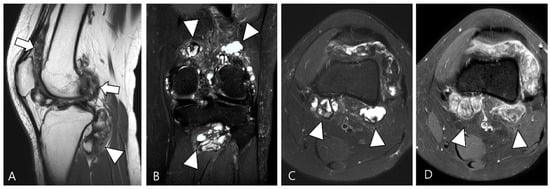

2.3. Morphological Findings for D-TSGCT

2.4. Relationship to Adjacent Structures of D-TSGCT